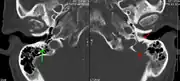

A CT of the brain revealed a lytic lesion in the left temporal bone (right side of image), and petrous temporal bones involving the mastoid segment of the facial nerve canal. Red arrows: lesion; green arrow: normal contralateral facial nerve canal. The lesions are consistent with a myeloma deposit.